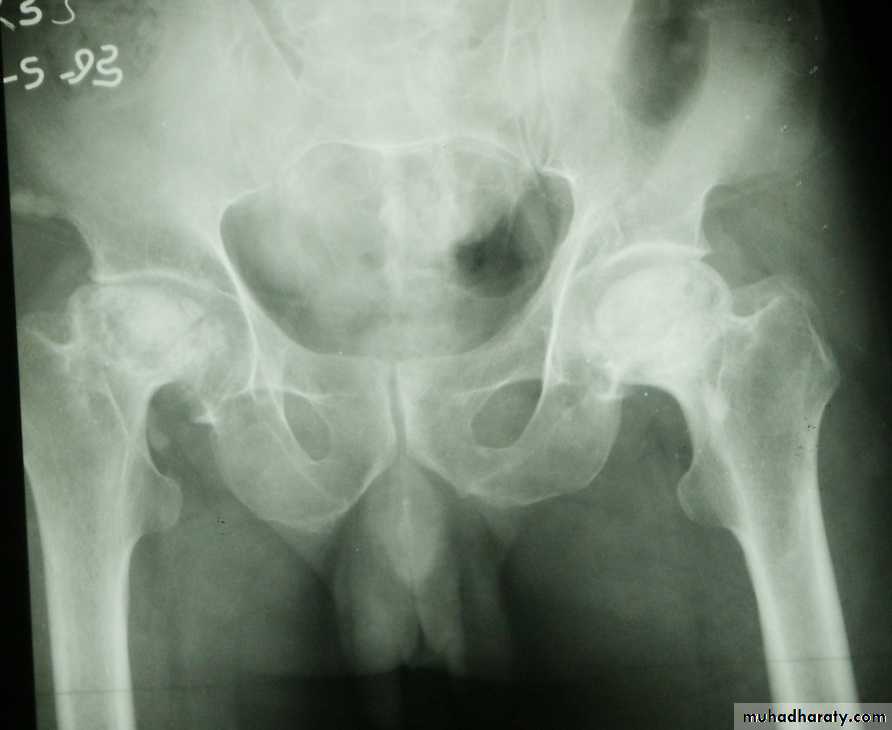

Posterior dislocation:

Mechanism of injure:4 out of 5 traumatic hip dislocations are posterior.

Usually occur in road traffic accident when the knee striking the dashboard

the femoral head is forced out of its socket sometimes associated with fracture.

The golden role is to x ray the pelvis in every case of sever injure

and with femoral fracture to include both the hip and knee.Radiological examinations

X-R AP view we can see the dislocation with or without associated fracture posterior wall of the acetabulum,or fracture head of the femur,

And neck of femur.

CT scan

is the best way of demonstrating acetabuluar fracture or any bony fragment.The dislocation must be reduced as soon as possible under general anesthesia. In the vast majority of cases this is done with closed reduction

Traumatic anterior hip dislocation:Mechanism :

Road traffic accident ,miner, building laborer who is leg wide .

knees straight .

Back bent forward.

Clinically:

O\ELeg external rotation.

Abducted and slightly flexed.

Bulging head seen laterally and also feel.

Hip movement impossible.

Neurovascular examination necessary.

Radiological examination:

Hip dislocated either superior, inferior in relation to the acetabulum.Treatment: